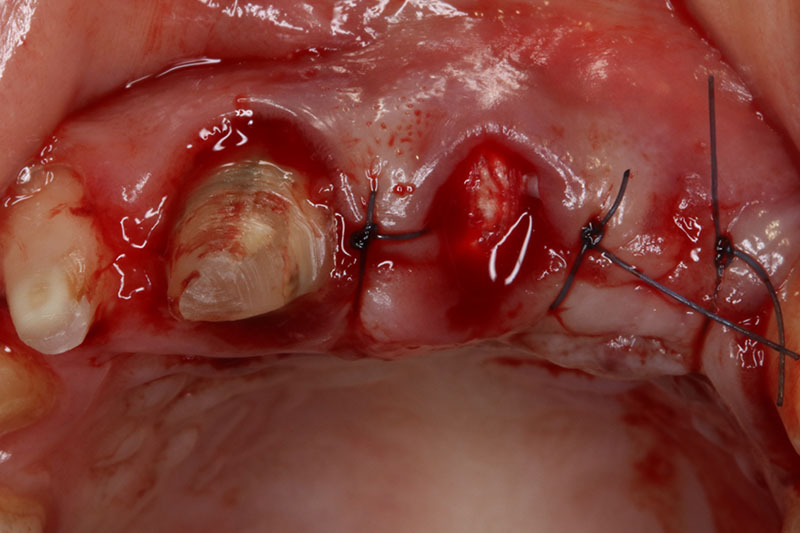

案例五

術中